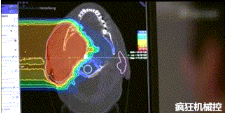

▲360°重離子治療一體機治療腫瘤

360°重離子治療一體可從任何角度用重離子(碳,氦,氧)和質(zhì)子(氫)照射腫瘤。此外,基于機器人的治療臺可以通過(guò)六種方式進(jìn)行調整。

光柵掃描被集成到360°重離子治療一體機中,這種極其精確的照射方法以毫米為單位掃描腫瘤,可以保護健康組織且只治療腫瘤區域。

特別是腫瘤在高度輻射敏感位置或者諸如視神經(jīng)附近的復雜位置,可以通過(guò)選擇最佳射束入射角來(lái)減小這些器官的損傷。